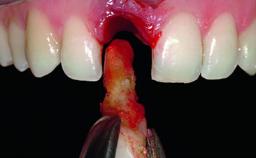

A healthy 28-year-old female patient presented for a consultation on treatment options to restore her upper right central incisor. At the clinical examination, the tooth responded to percussion and palpation. The gingiva was red and slightly swollen, with a mid-facial probing depth of 10 mm. The upper right lateral incisor showed no signs or symptoms, did not respond to exploration and percussion, and the vitality test was positive. The periapical radiograph revealed that tooth 11 had been endodontically treated, with no lesion evident at the apex. A small radiopaque calcified structure surrounded by a narrow radiolucent zone (3 × 3 mm) was present at the apex of tooth 12.